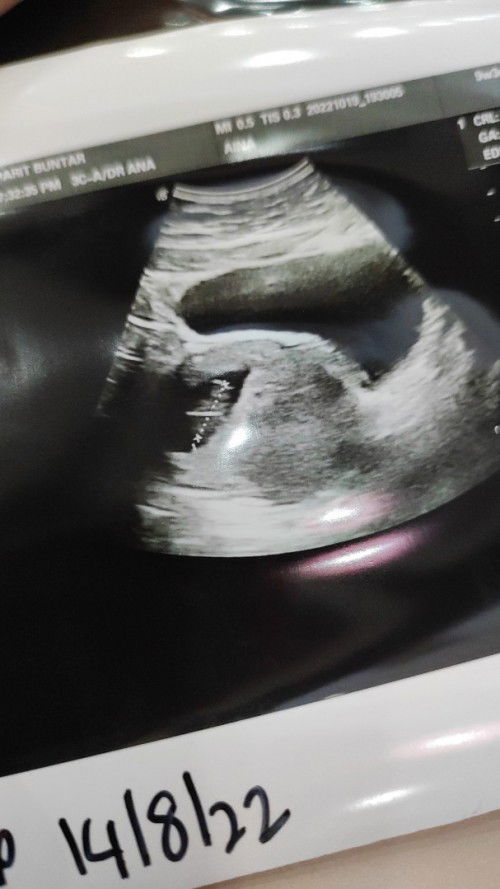

Baby 11 week

Hi ibu ibu normal kee... 11w baby npk kcik sebp perut tebai msa scan kk... Doc ckp ok jaa ...doc suh repeat scan dekt kk 18w pulkk